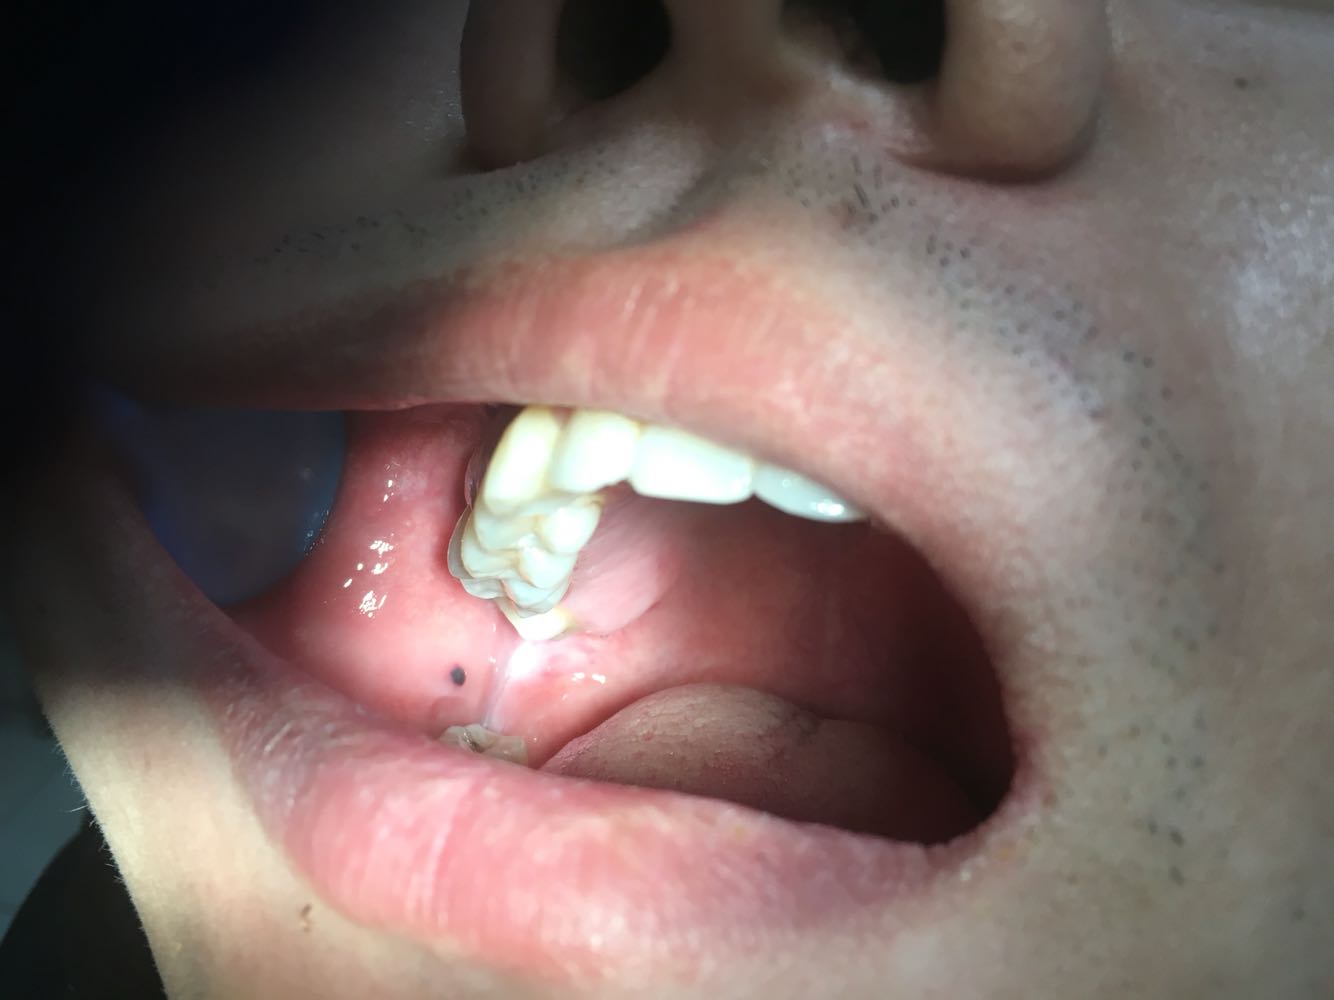

检查:右侧腮腺区以耳垂为中心肿大,按压疼痛明显,皮温微高,无发红,导管口轻度红肿、疼痛,无脓性分泌物,血常规检查:WBC.11.09↑,NEUT#.7.27↑MONO#.0.81↑AMY.30

诊断:细菌性腮腺炎 治疗:抗炎治疗,局部注意口腔卫生,ct排除涎石可能性,密切观察,如果出现腮腺导管口溢脓可进行细菌培养及药敏,根据药敏调整敏感抗生素。